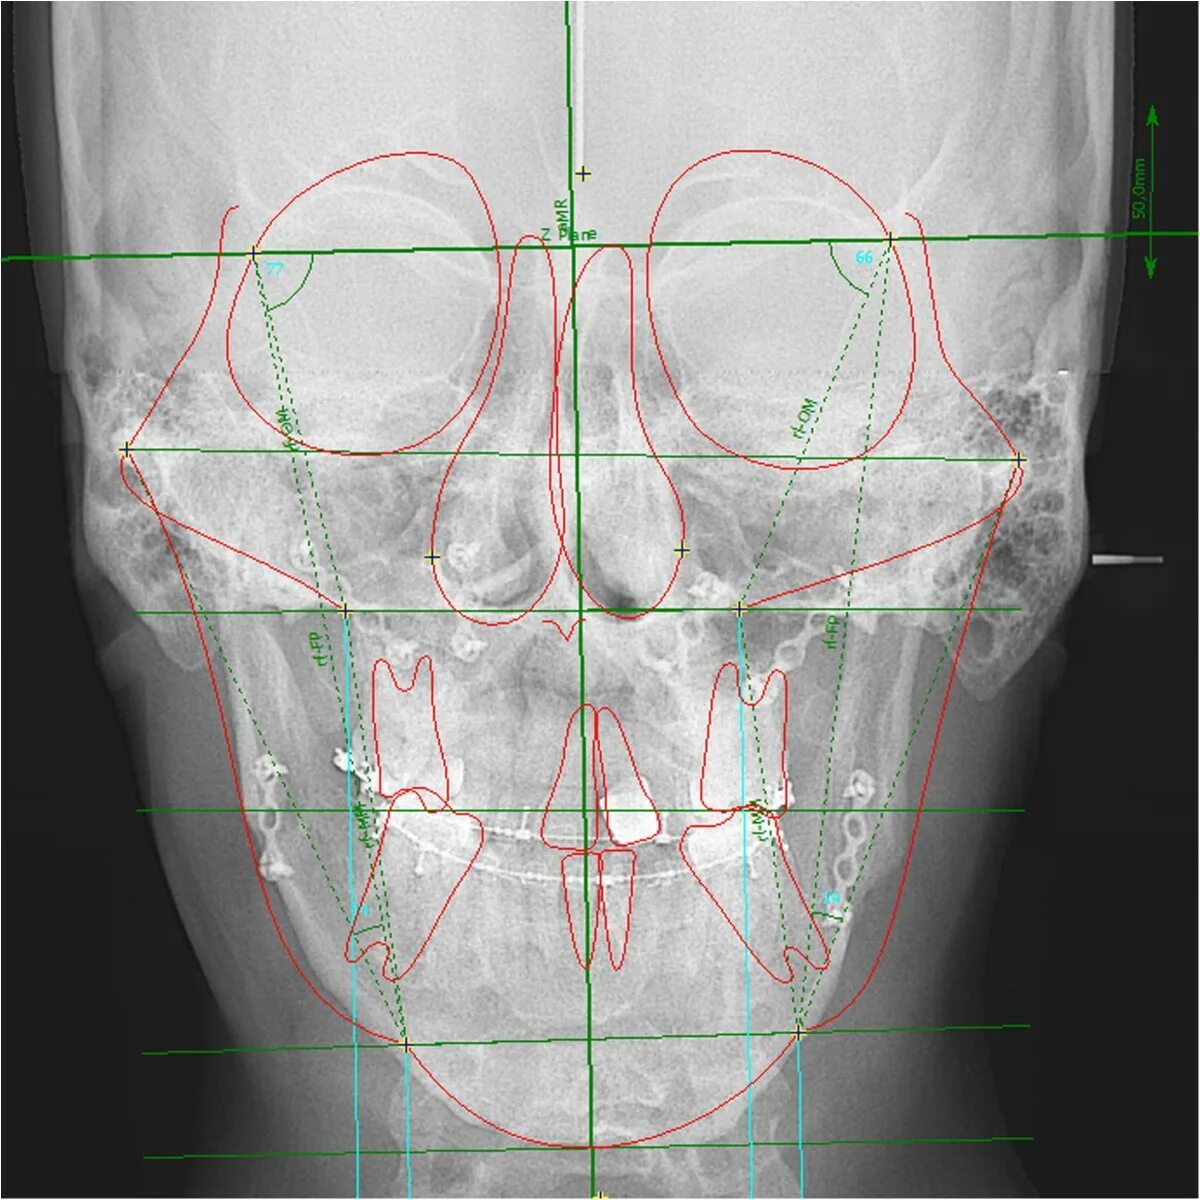

Остеопатия череп